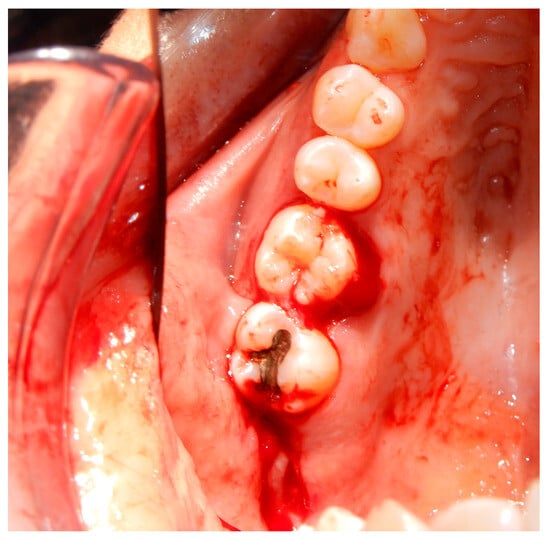

3.2. Case Report